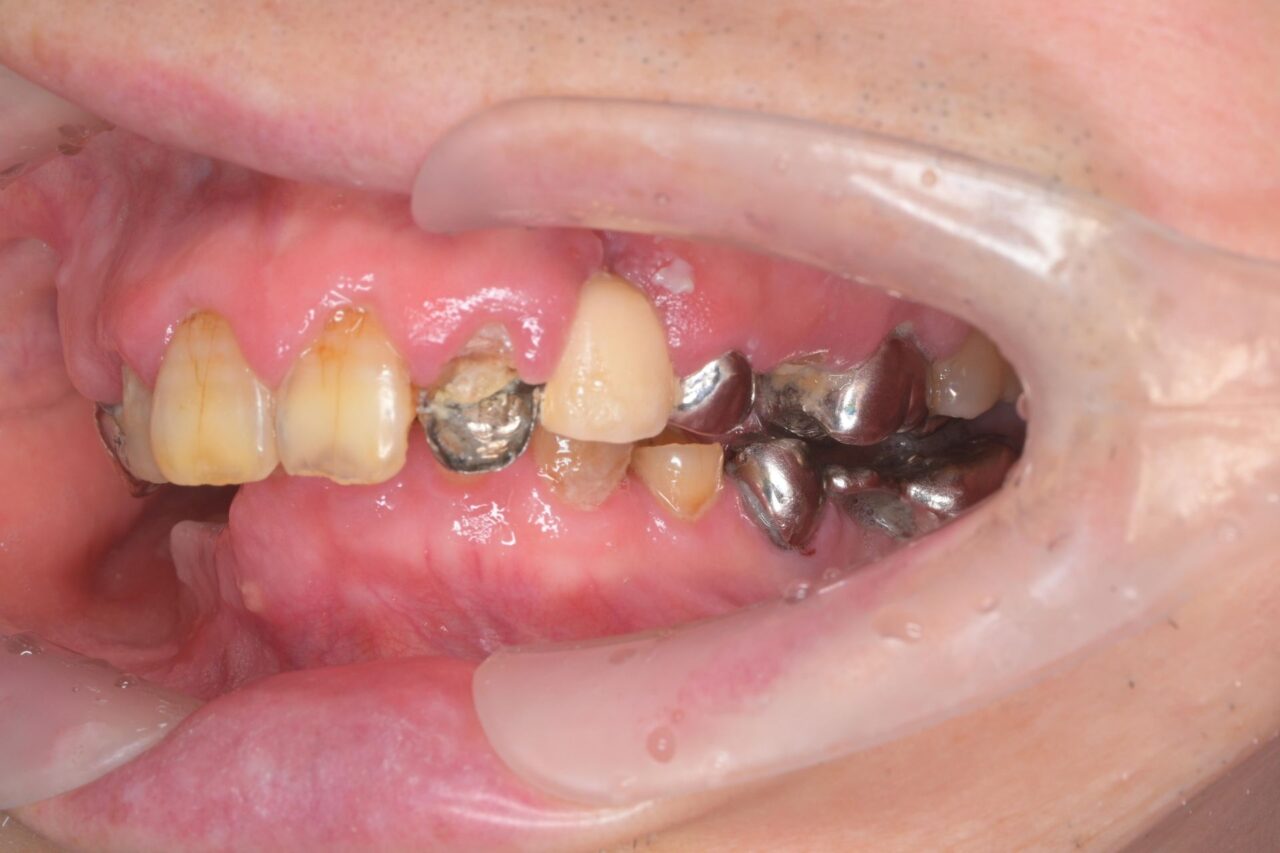

左側

一見、左側は歯があるように見えますが、ブリッジが入っていてかぶせ物の中が完全に虫歯でやられてしまっています。(レントゲン写真で確認済み)

歯科治療において、ブリッジは絶対にやってはいけません!!!!!!!